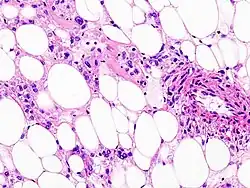

| Histopathologic image of renal angiomyolipoma. Nephrectomy specimen. H&E stain. | |

PECs consist of perivascular epithelioid cells with a clear/granular cytoplasm and central round nucleus without prominent nucleoli.